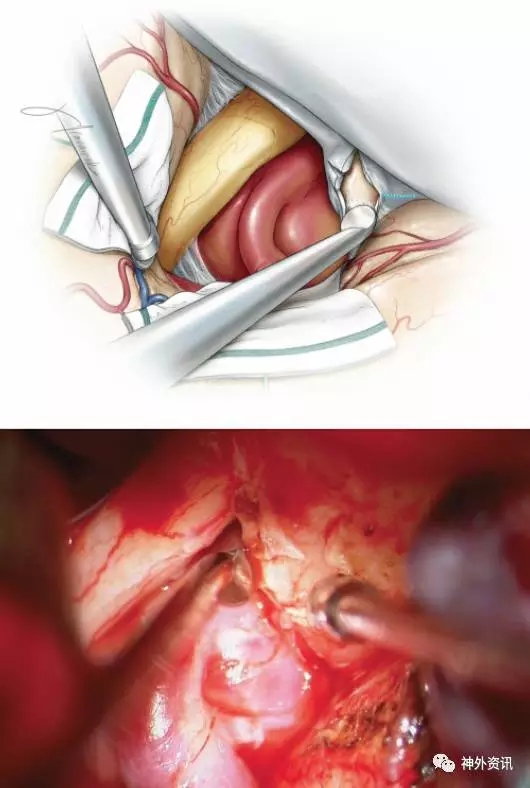

图8. 使用金刚钻,在持续冲水下磨除前床突。也可使用超声骨凿。这一步骤中,骨质磨除的范围可根据需要而定,目的是充分暴露出被前床突遮挡的近端部分瘤颈。需保留一薄层骨壳作为保护颈内动脉和动脉瘤的安全界面。内侧硬脑膜辦也起到了保护这些重要结构的作用。在本示意图中,只需磨除内侧少量的前床突骨质即可实现瘤颈的充分暴露,因此无需行完全性的前床突切除术。

对于那些动脉瘤侵蚀前床突并与之粘连的病例,需保留一薄层骨片于瘤顶,随后即将注意力集中在瘤颈的暴露。

图9. 前床突内部已被充分磨除;该操作即可使其与视神经管和视柱相离断。残余的薄层骨壳可从各床突韧带上钝性分离并去除。静脉性出血可通过脑棉及小片凝血酶化的明胶海绵轻轻压迫来轻易控制。经过这一前床突内侧部切除术后,即可充分暴露极端部分的瘤颈,此时即可行动脉瘤夹闭(上图,插图)。在瘤颈部也可实现颈内动脉近端控制。

必要时,可继续沿着颈内动脉壁进行分离,暴露并切开远环,以显露颈内动脉床突段。

图10. 一例右侧巨大后交通动脉瘤的术中图片,瘤颈的近端部分已被充分显露。